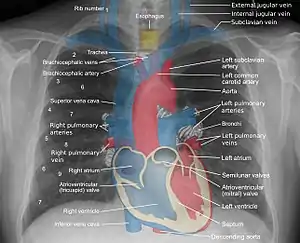

A chest radiograph, called a chest X-ray (CXR), or chest film, is a projection radiograph of the chest used to diagnose conditions affecting the chest, its contents, and nearby structures. Chest radiographs are the most common film taken in medicine.

Chest radiographs are used to diagnose many conditions involving the chest wall, including its bones, and also structures contained within the thoracic cavity including the lungs, heart, and great vessels. Pneumonia and congestive heart failure are very commonly diagnosed by chest radiograph. Chest radiographs are also used to screen for job-related lung disease in industries such as mining where workers are exposed to dust.[3]